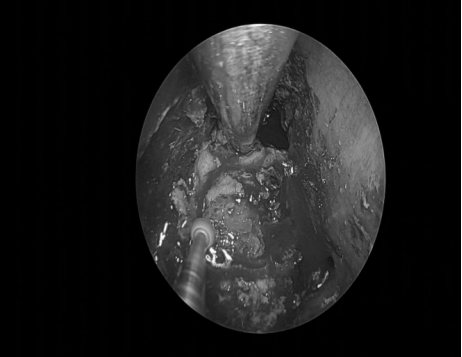

手术经过

3、鼻内镜入路:包括经翼突入路、经上颌窦入路、经口入路。蝶骨翼突起于蝶骨体与蝶骨大翼交接处下方,分成翼内板和翼外板。翼内板和翼外板的前上部融合,下部分离形成翼切迹,与腭骨锥突连接。

翼内板和翼外板之间称为翼窝,为翼内肌的起始处。鼻内镜入路优点在于不损伤听力、颜面部无切口,但手术操作仍有许多困难,要求手术操作者磨除翼突时应十分熟悉翼腭窝、颞下窝的解剖结构。